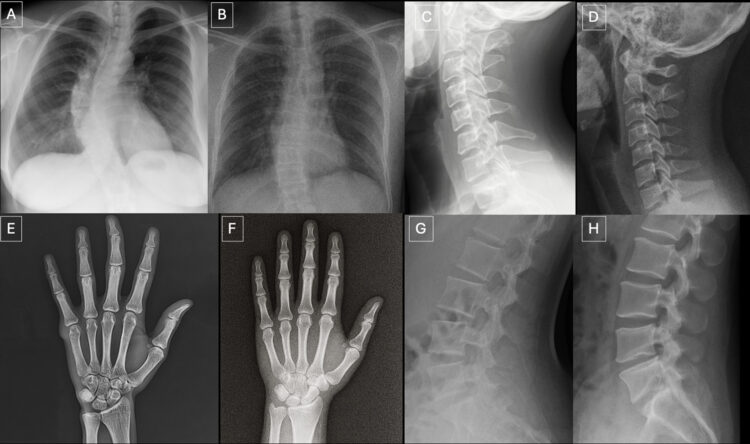

사전 정보 없으면 전문의도 가짜 구분율 41%, 알려줘도 75%

이런 상황에서 영상 전문의는 AI가 만든 딥페이크 의료영상을 얼마나 구별하며, AI는 다른 AI가 만든 가짜 영상을 얼마나 알아차리는 지를 알아보는 연구 결과가 나왔다.

미국에서 영상의학 전문의들에게 실제 환자의 X-선 사진과 AI가 생성한 가짜 영상을 각각 보여줬더니 사전 고지 없이도 스스로 ‘가짜 영상’을 구별해낸 전문의의 비율은 41%로 나타났다. 절반이 안되는 수치다. AI 영상이 포함됐다고 알려준 상태에서 가짜 영상과 실제 사진을 정확하게 구별해낸 비율은 75% 수준이었다.

이는 미국 뉴욕시 소재 마운트사이나이 아이칸 의대의 바이오의공학 및 영상 연구소의 의사과학자 마이클 토지만 박사 연구팀이 6개국 영상 전문의 17명을 대상으로 연구한 결과다. 연구팀은 모두 264장의 X-선 사진을 3단계에 걸쳐 보여주며 판별 여부를 살폈다. 연구팀은 그 결과를 의학학술지 ‘방사선의학(Radiology) 최신호에 게재했다. ‘딥페이크 의료 영상의 부상: ChatGPT로 생성된 방사선 사진을 탐지하는 방사선 전문의의 진단 정확도(The Rise of Deepfake Medical Imaging: Radiologists’ Diagnostic Accuracy in Detecting ChatGPT-generated Radiographs)‘라는 제목이다. 이 연구는 AI의 발달에 걸맞은 의학 교육·수련 시스템의 재정비와 의료법·행정 등 제도적 장치의 필요성을 잘 보여준 것으로 평가된다.

연구는 3단계로 나눠 진행됐다. 1단계에서는 AI 생성 이미지 77장과 진짜 실제 이미지 77장 등 154장을 영상의학과 전문의들에게 제시해 화질을 평가하고 진단을 내리게 했다.

2단계에선 영상의학 전문의들에게 AI 이미지가 포함됐음을 알린 뒤 무작위로 제시된 X선 사진이 지피티-4o로 생성된 것인지 실제 이미지인 지를 판별하게 했다. 이와 함께 4가지 AI 프로그램에 같은 판별 작업을 하게 했다. 3단계에선 추가로 AI 합성 55장과 실제 영상 55장 등 모두 110장의 흉부 X선 사진을 제시해 전문의와 AI의 판독 능력을 통계적으로 분석했다.

사전정보를 제공하지 않은 상태에서 영상 전문의 17명 중 7명(41%)이 데이터 중에 AI 생성 영상이 있음을 스스로 알아차렸다. 일부 영상이 AI 합성이라는 사실을 알려준 뒤 전문의들에게 진짜와 가짜를 골라내게 했더니 평균 적중률이 75%로 나타났다. 민감도(진짜를 진짜로 골라낸 비율) 69%. 특이도(가짜를 가짜로 골라낸 비율) 80%였다.

진짜와 가짜를 판별하지 못하는 것은 AI 프로그램도 마찬가지였다. AI 프로그램에 진짜 영상과 AI 합성영상을 제시해 구별해보라고 했더니 지피티-4o는 85%, GPT-5는 83%, 라마4매버릭은 59%, 제미나이2.5프로는 56%를 각각 실제 영상과 구별했다.

부자연스러운 조직 질감, 매끄러움 등 AI 가짜영상 구분법 발견

연구팀은 AI 가짜 영상을 분석한 결과 뼈가 지나치게 매끄럽다든지, 조직의 질감이 미미하게 부자연스럽다든지, 균일한 노이즈(불필요한 알갱이나 거친 입자, 불규칙한 색상이나 얼룩)가 나타나는 등 공통점을 발견할 수 있었다고 지적했다. 이런 노하우를 축적해 교육·수련 등에 사용할 수 있다는 의미다.